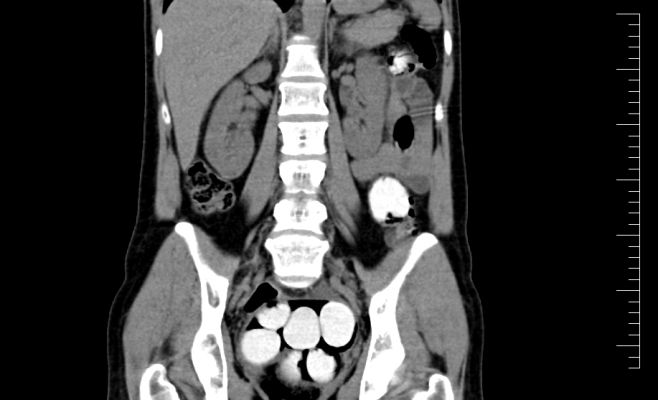

Ренген тела задержанного | Автор: Celní správa České republiky

Таможенная служба международного аэропорта Вацлава Гавела произвела задержание 48-летнего иностранного гражданина, который попытался ввезти в Чехию в своём теле 112 капсул кокаина, что соответствует 1,2 кг.

Мужчина прилетел в Прагу из Мадрида. Столичная таможенная служба располагала информацией о том, что в рейсе из Мадрида находится преступник, пытающийся ввести контрабанду. Сотрудники аэропорта изучили багаж каждого пассажира, но попался преступник только на том, что на его руках были обнаружены мельчайшие элементы наркотических веществ, затем его отправили на рентген.

«Постепенно мужчина достал из своего тела 112 капсул. Дальнейшая экспертиза показа, что это кокаин», – рассказала пресс-секретарь таможенной службы.